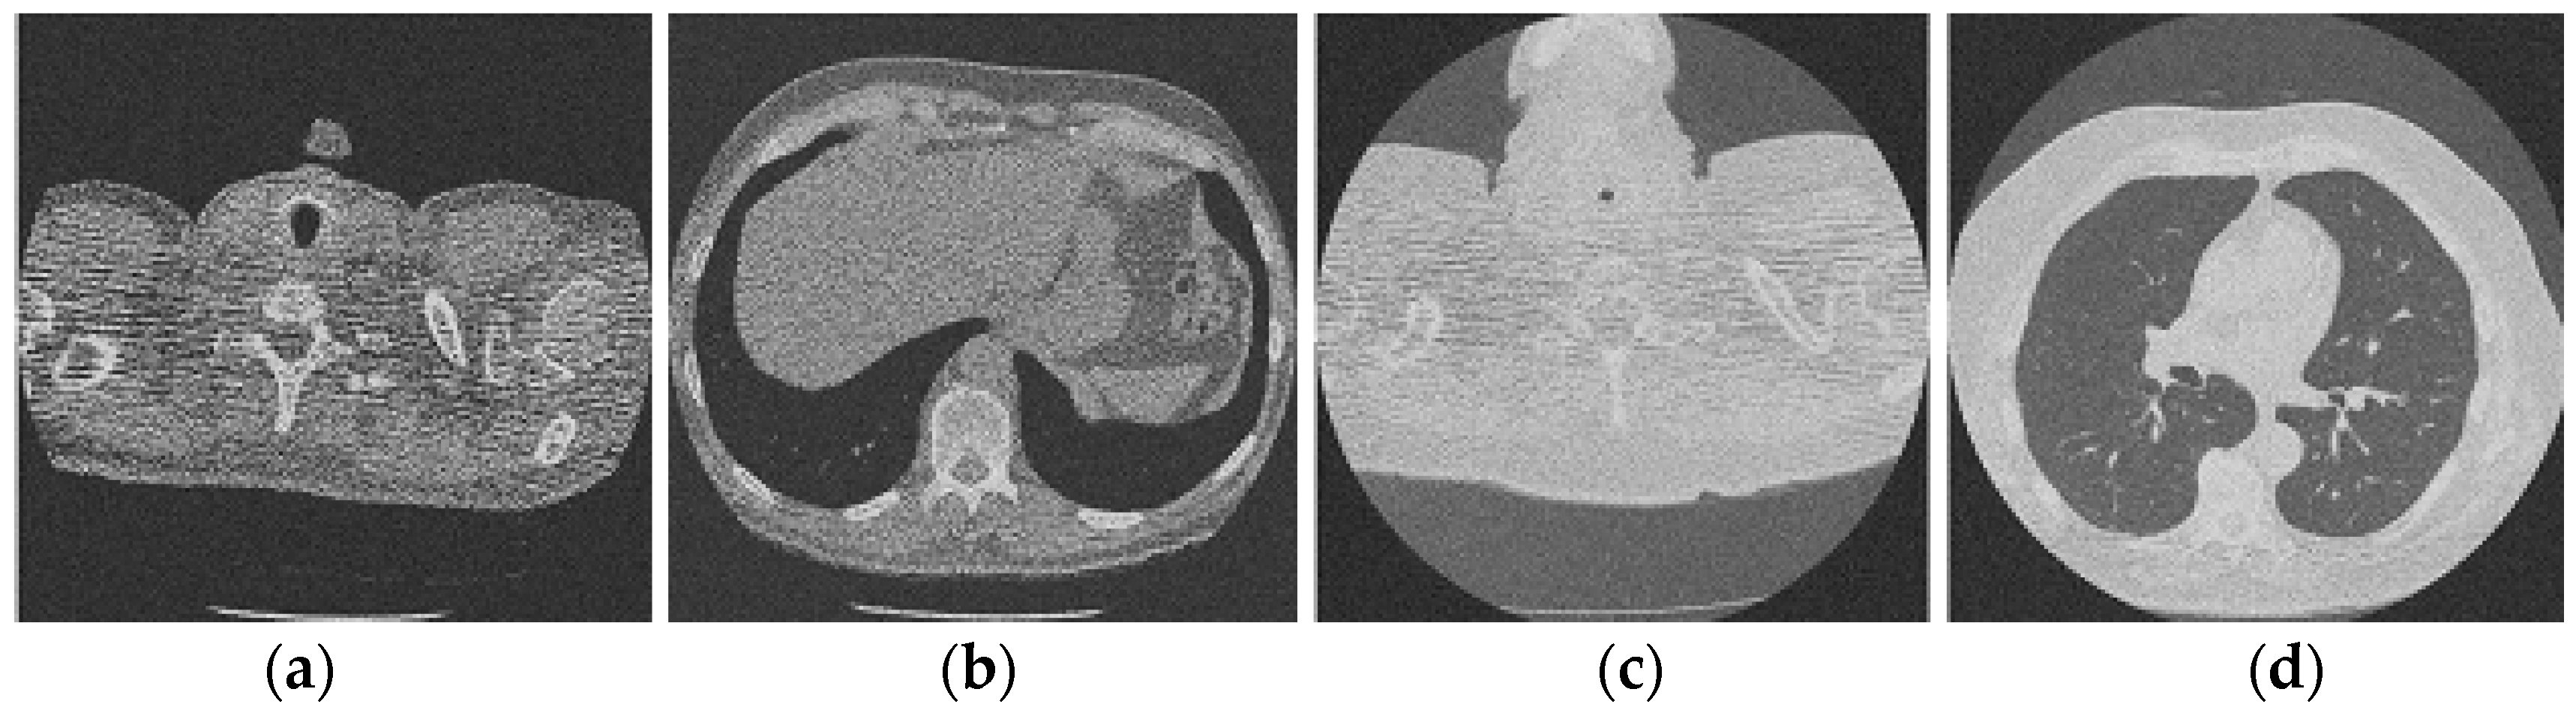

Figure 3 shows the corruption of a CT image after the addition of 20% Gaussian noise. The degradation in image quality is visible to the naked eye without aid when compared to the original CT image. Figure 4, Figure 5, Figure 6, Figure 7, Figure 8, Figure 9, Figure 10 and Figure 11 show the denoised CT images, corresponding to CT images in Figure 3 and generated from various denoising models. The results show a discernible reduction in both the gaussian noise introduced, as well as the noise present in the original CT image whilst safeguarding the finer details present in it.

Figure 3.

Noisy CT image data set after inserting 20% noise); (a) Noisy CT1 image; (b) Noisy CT2 image; (c) Noisy CT3 image; (d) Noisy CT4 image.